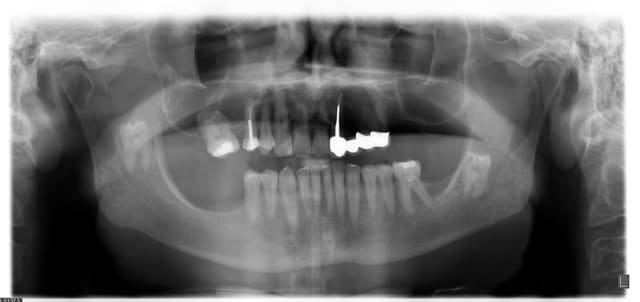

Que pensez vous de cette 18 dont une cuspide apparaît en bouche? Patiente de 18 ans. Que serait votre abord chirurgical face au risque de la projeter dans le sinus, ou comment gérer la couronne cariée

1-Pano

2-L'exo ne semble pas si compliquée, mais pas facile si c'est ta 3e....

Jolies les 38 et 48

Pano 38 48 esjjvx - Eugenol